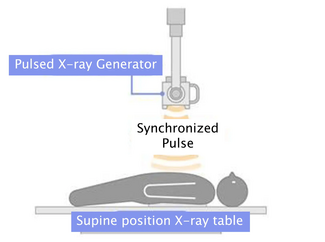

Case Report. A 75-year-old male with a history of coronary artery disease status post 2-vessel CABG 8 years prior [LIMA to middle left anterior descending (LAD) coronary artery and saphenous vein graft to the first obtuse marginal coronary artery] was referred for cardiac catheterization with a history of atypical chest discomfort and an anterior perfusion defect on adenosine sestamibi stress testing. His past medical history was notable for symptomatic bradycardia necessitating permanent pacemaker implantation, hypertension, hyperlipidemia, former nicotine abuse with a 30-plus pack-year smoking history, bilateral renal artery stenosis status post renal artery stenting, and severe aortoiliac occlusive disease status post aortobifemoral bypass. The adenosine sestamibi revealed a new perfusion defect anteriorly in the distal one-third of the ventricle and apex when compared to a study 1 year prior. Left ventricular function by gated wall motion was 48%, with a subsequent transthoracic echocardiogram demonstrating a left ventricular ejection fraction of 65% with no regional wall motion abnormalities or significant valvular abnormalities.

Case Report. A 75-year-old male with a history of coronary artery disease status post 2-vessel CABG 8 years prior [LIMA to middle left anterior descending (LAD) coronary artery and saphenous vein graft to the first obtuse marginal coronary artery] was referred for cardiac catheterization with a history of atypical chest discomfort and an anterior perfusion defect on adenosine sestamibi stress testing. His past medical history was notable for symptomatic bradycardia necessitating permanent pacemaker implantation, hypertension, hyperlipidemia, former nicotine abuse with a 30-plus pack-year smoking history, bilateral renal artery stenosis status post renal artery stenting, and severe aortoiliac occlusive disease status post aortobifemoral bypass. The adenosine sestamibi revealed a new perfusion defect anteriorly in the distal one-third of the ventricle and apex when compared to a study 1 year prior. Left ventricular function by gated wall motion was 48%, with a subsequent transthoracic echocardiogram demonstrating a left ventricular ejection fraction of 65% with no regional wall motion abnormalities or significant valvular abnormalities.